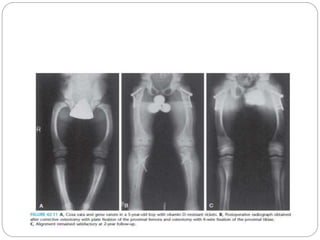

 The orthotic management of vitamin D–resistant

rickets has not been efficacious.

 The deformity most commonly seen in patients

with hypophosphatemic rickets is a gradual

anterolateral bowing of the femur, combined with

tibia vara.

Vitamin D–Resistant Rickets

 Multilevel osteotomy is generally required to

satisfactorily correct the mechanical axis of the

limb.

 The mechanical axis should be mildly

overcorrected at surgery

 The suggested fixation varies among reports.

External fixation allows fine tuning of the

alignment postoperatively, when the patient is

able to stand

 Others advocate the use of intramedullary fixation